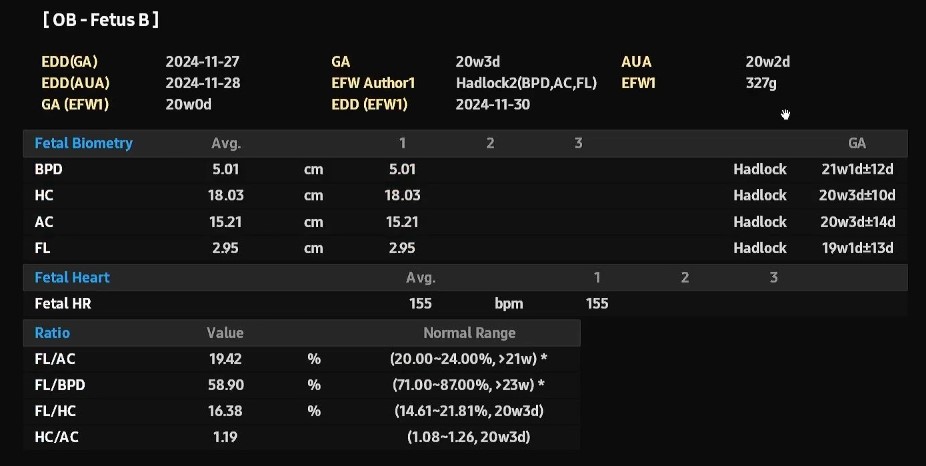

쑥쑥이는 377g, 쭉쭉이는 327g으로 둘의 차이는 13.09%로 저번보다 차이는 많이 나지만 20%넘으면 안좋다고 하셨어요.